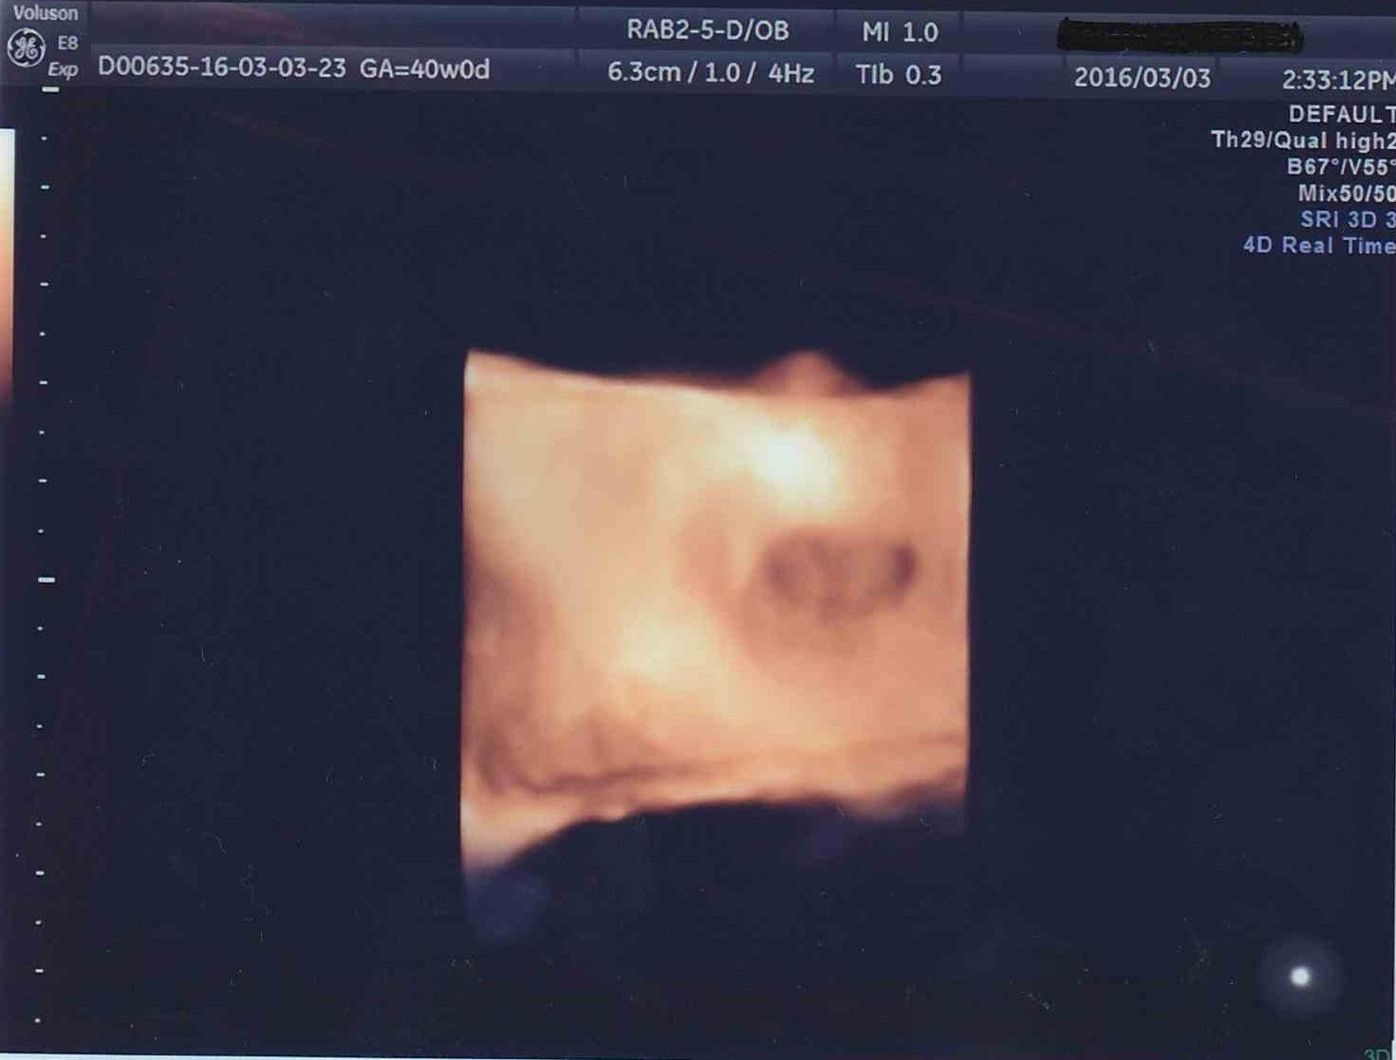

テーマ: ふー妊娠6ヶ月~7ヶ月* 先週の金曜日に初 4Dエコー に行ってきました ウチの病院は4Dはいつもの先生じゃなくって、 専任の技師さんが担当してくれるのですが、 予約が平日の午後しかなくって、ダンナと休暇エコーの写真だけでなく4dもやってる病院で、健診がすごく楽しみでした。 顔がエコーに映っていないと、写真はもらえませんでした。 果たして胎児は男の子なのか、女の子なのか。エコーでいつ、どんなふうに性別がわかるの? オービス 1 :名無しさん:(日) IDd//URnS5net って、速度超過で通り過ぎても、稼働しない場合があるん

こんな感じで、初めての4Dエコーにとても感動して親バカが炸裂しました。 臨月になると、赤ちゃんにも脂肪がついてぎゅうぎゅうで入っているようで。 あの日見た美少女はどこへ? と戸惑いながらも冷静さを取り戻しました(笑) 実際生まれてきお子さんの可愛いエコー写真見せて下さい♡ 私のお気に入りのエコー写真です。 女の子です♡ 4Dエコーと同じ顔で産まれてくるのかどうか楽しみです٩ (ˊᗜˋ*) 2月22日 お気に入り 女の子 エコー写女の子は妊娠7ヶ月で判明が多い妊娠24週~26週のエコー写真 妊娠7ヶ月頃になると、多くの産院でエコー検査にて性別を調べてくれるようになります。 (産院の方針や妊婦の状況にもよる) この頃になると男の子のシンボルがエコーで見えない

4Dエコー全記録写真付き! おすすめの時期や気になる費用 追記 38週まで写真も追加しました 生まれてくる赤ちゃんはどんな顔をしているんだろうと日々妄想する私。 夫に似ているのかな、私に似ているのかな。 (夫に似てほしいー! ! ) と 4dでは、赤ちゃんが指をしゃぶる仕草まで確認することが出来ます。 2d、3d、4dエコーにはそれぞれ以下のような特徴があります。 2dのエコーとは 縦と横に超音波をあてて、返ってきたデータを映像化し平面的に赤ちゃんを見られるエコーです。『他院で4dエコーを予約しました』 こんにちは 先日、週のときに4dエコーをして頂いた記事を書いたのですが 体感3分くらいで、写真もカラーのものを1枚やっていただいたのは嬉しかったです